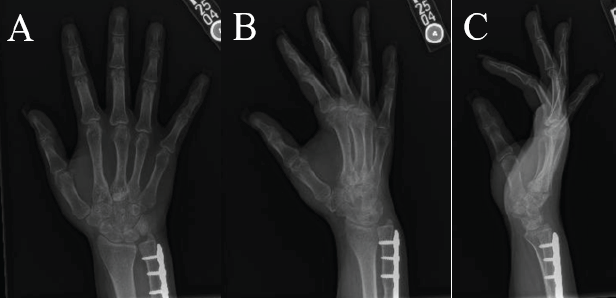

At 5 months post-operation, the patient returned for hardware removal. At that time, the patient’s MCP joint motion had improved: Index finger flexion of 45°, and middle, ring, and small finger MCP joint flexion to 70°. Six weeks post-hardware removal, the patient’s motion had improved to 60° of flexion in the index finger, while MCP joint motion in the other fingers remained unchanged (Fig. 5). Wrist range of motion was 45° flexion and 50° extension. Three months post-hardware removal, the patient was doing well and using her hand normally (Fig. 6). Final DASH score at 1 year postoperatively was 2.5.

Figure 5: Six weeks status post removal of hardware of the right hand.

Figure 6: Three months status post removal of hardware radiographs of the right hand. (a) posteroanterior view, (b) oblique view, (c) lateral view. X-rays show appropriate healing post removal of bridge plating of the second and third metacarpals with fixation of ulna shaft fracture.